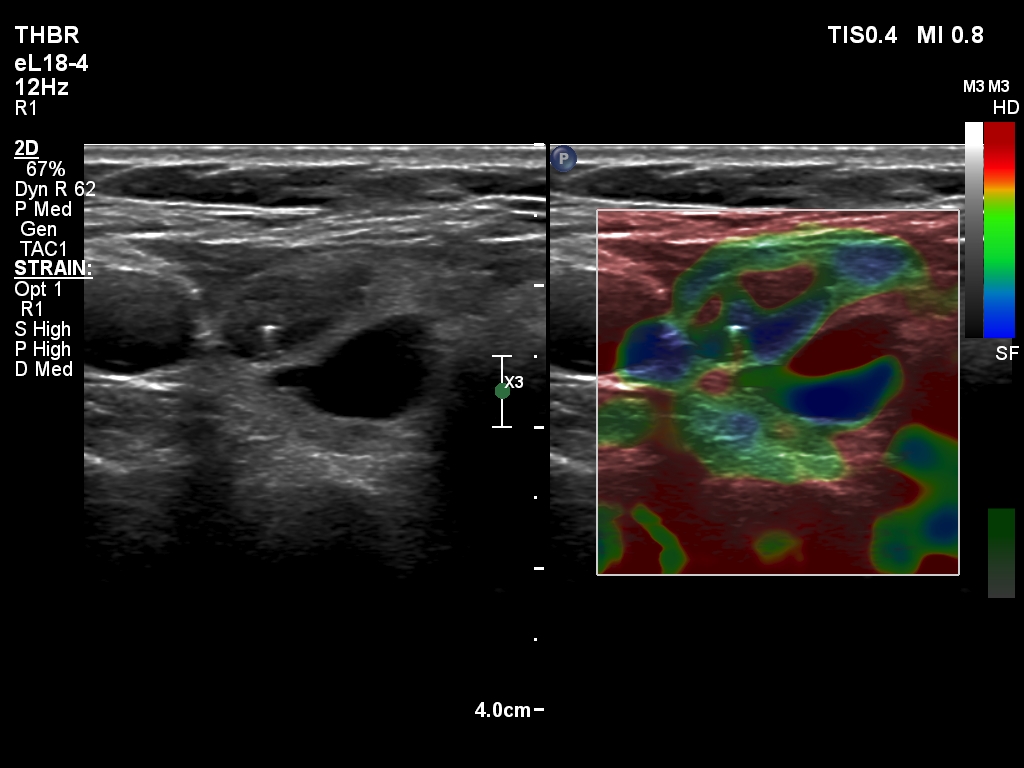

Ultrasonography. The thyroid was echonormal and had multiple nodules. There were cystic areas, an almost completely cystic nodule, and a dominantly solid nodule in the right lobe. The left lobe had three lesions. The upper solid lesion was the one we treated 16 years ago. The middle lesion was a dominantly solid while the lower one seemed to be a pure cyst. The dimensions of the nodule which has been treated with sclerotherapy were 10x11x13 mm (width, depth and length, respectively). There was a large cystic nodule in the upper pole of the left lobe. The lesion showed relatively large hyperechogenic granules. There were multiple enlarged lymph nodes lateral to the left lobe, two of largest were cystic.